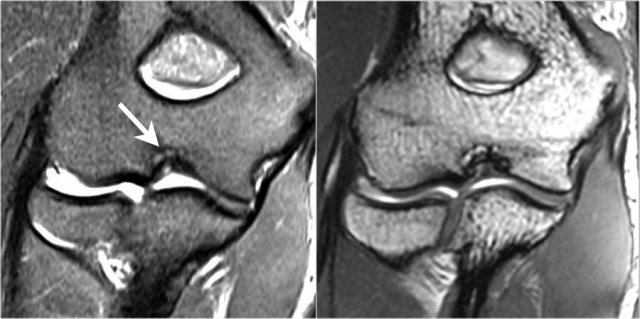

OC lesion of trochlea

These images are of a patient with anterior elbow pain.

There was no recent injury.

The clinical diagnosis was a biceps tendinitis or a bicipital bursitis.

The findings on the coronal MR-images are quite uncommon.

If you would see this in the capitellum you would call it an osteochondral lesion of the capitellum.

So this is called an osteochondral lesion of the trochlea.

Notice the small cystic changes (white arrow).

There is also a small cartilage defect.

An osteochondral lesion of the trochlea is usually seen in younger patients, who have an immature skeleton.

It is seen in the lateral trochlea like in this case due to repetitive hyperextension in an area with tenuous blood supply.